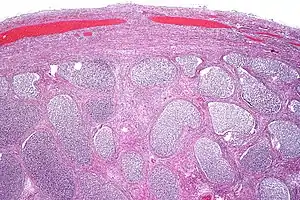

![]() | |

Acute epididymitis with abundant fibrinopurulent exudate in the tubules. | |